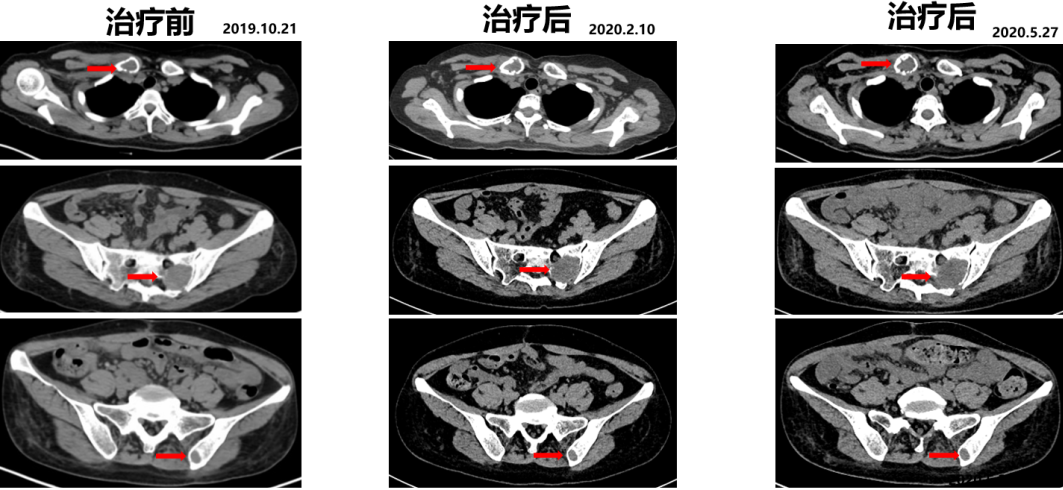

2019.10.21开始舒尼替尼50 mg po QD治疗(4/2方案)。

2020.05.27复查PET-CT病灶稳定,代谢较治疗前明显减低。影像学评估SD。

△舒尼替尼治疗后病灶稳定,代谢较治疗前明显减低

一线PFS:25个月。